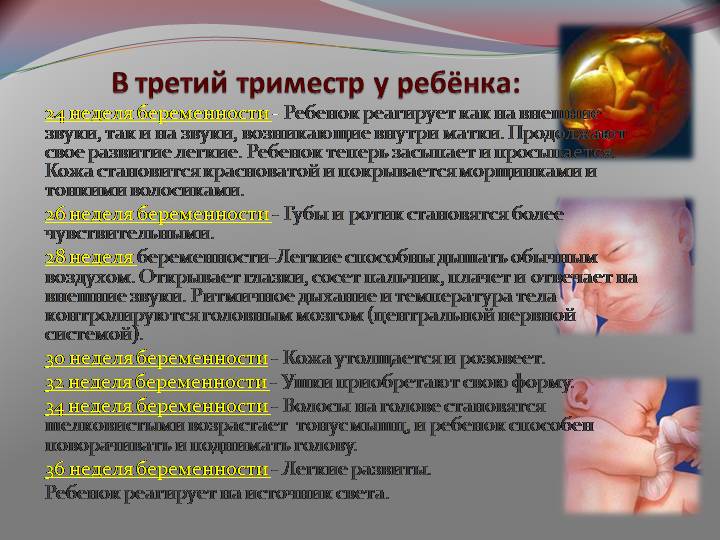

Фотографии и советы по третьему триместру беременности

Раздел: Точки зрения